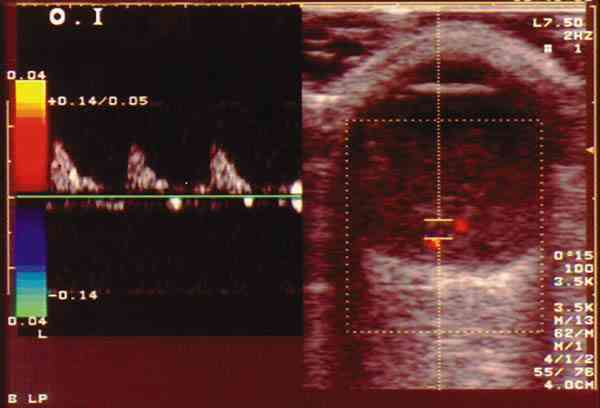

Figura 2. Retinoblastoma parcialmente calcificado que llega hasta el

cristalino. Mediante el color se aprecia vascularización intratumoral.